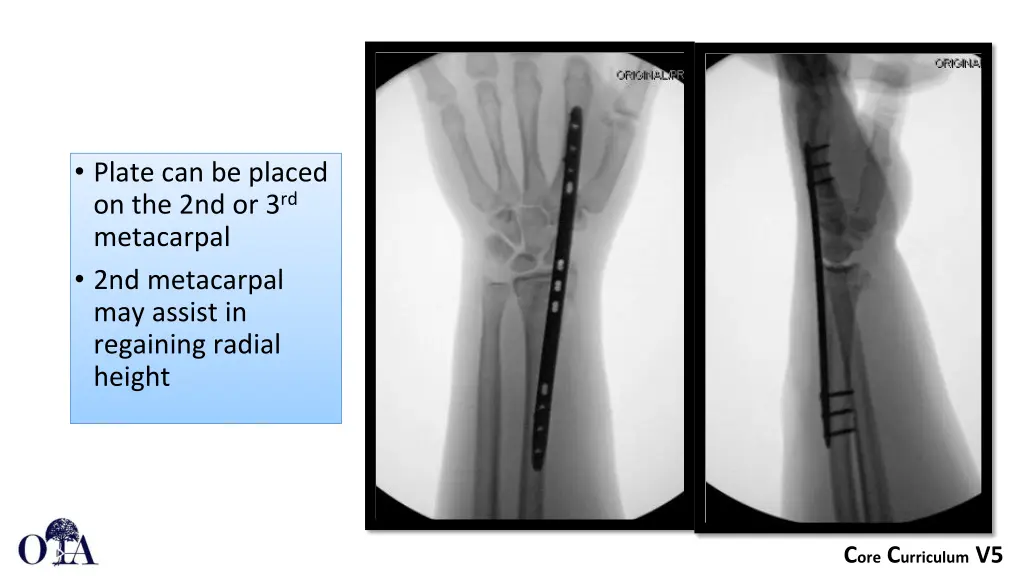

Plate can be placed on the 2nd or 3rd metacarpal 2nd metacarpal may assist in regaining radial height Core Curriculum V5